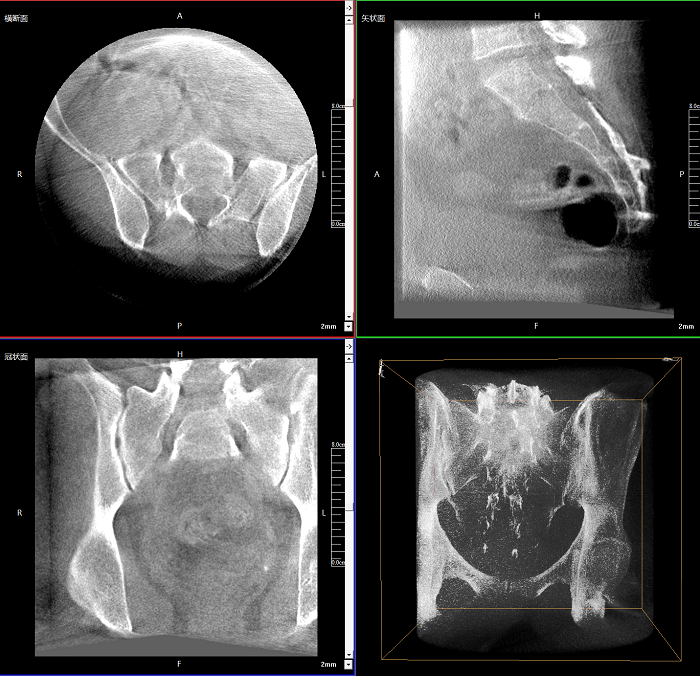

該設(shè)備可進(jìn)行快速的術(shù)中三維掃描,生成類CT斷層圖像和立體3D圖像,保障植入物置入效果。廣泛適用于骨科、脊柱外科、矯形外科、創(chuàng)傷骨科等其他領(lǐng)域。

●極速成像僅需8秒,從數(shù)據(jù)采集結(jié)束到完成三維重建斷層影像